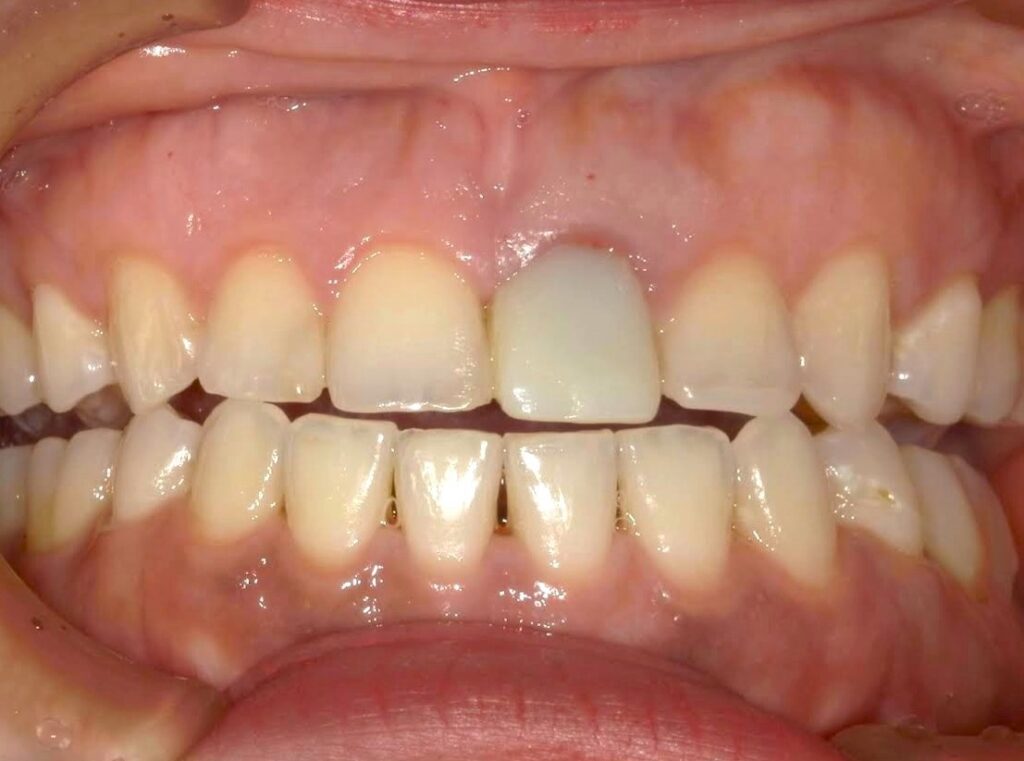

【A様】

Before

After

年齢 | 30代前半 |

性別 | 女性 |

主訴 | 前歯の被せ物の色味が合っていないのでやり直したい |

施術内容 | 色があっていない保険適応のCAD/CAM冠を外して、自費補綴のジルコニアに被せなおしています。 |